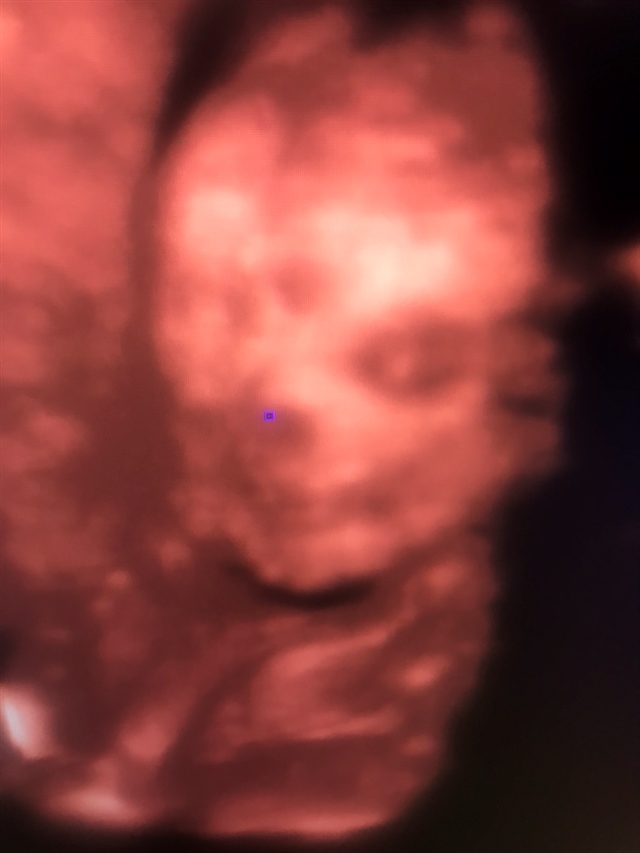

孕25周+3天

是头胎,还不知道男孩女孩

孕16周+6天